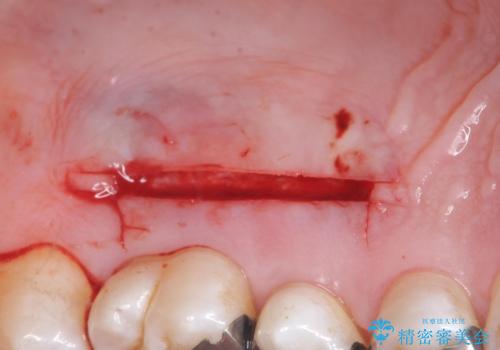

退縮した歯茎に対して移植をすることで、しみる場所を覆う計画です。

歯根の分岐部よりも根尖側の頬側面が露出している状態でしたが、露出部位を分岐部までに抑えることができました。